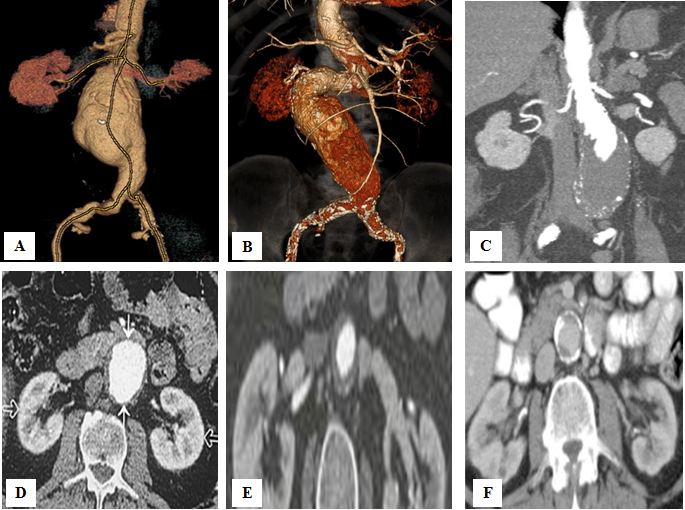

Figure 1. Hostile aneurysm neck anatomy that prevents the performance of standard EVAR.

A) Length <10 mm. B) Angulation >75⁰. C) Conical neck. D) Width >32 mm. E) Circumferential thrombus. F) Circumferential calcifications.